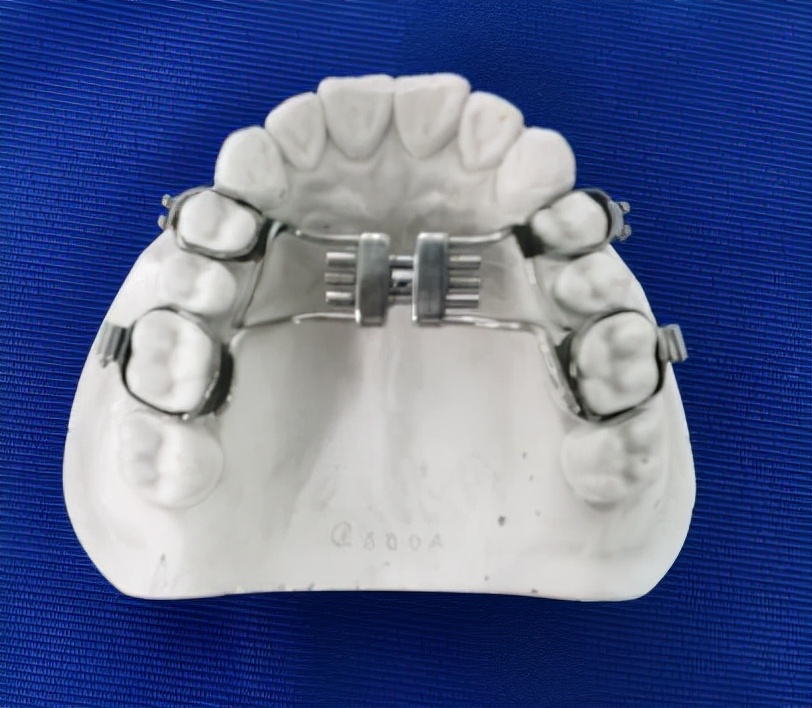

可以看到患儿的下巴是偏斜的,面部不对称。经检查发现患儿口内可见多颗乳磨牙龋坏,有偏侧咀嚼习惯,存在颌骨发育的不对称。这种严重的骨性畸形需要双期矫治。第一期早期矫治,其目的是去除病因及干扰因素,让上下颌骨的生长导向正常,从矢状向、横向、垂直向去改善上下颌骨的不调。该患儿首先应用的是矫形力矫治器(螺旋扩弓器),协调上下颌骨宽度,去除锁合侧咬合干扰,建立双侧后牙咬合,治疗乳磨牙龋坏,同时指导患儿用双侧咀嚼食物促进咀嚼肌平衡发育。然后应用的是FRⅢ功能矫治器,解除前牙反合改善下颌偏斜,FRⅢ的作用原理是去除导致颌骨畸形的功能因素而且可以改善轻度的骨性错合。

(图为扩弓矫治器)